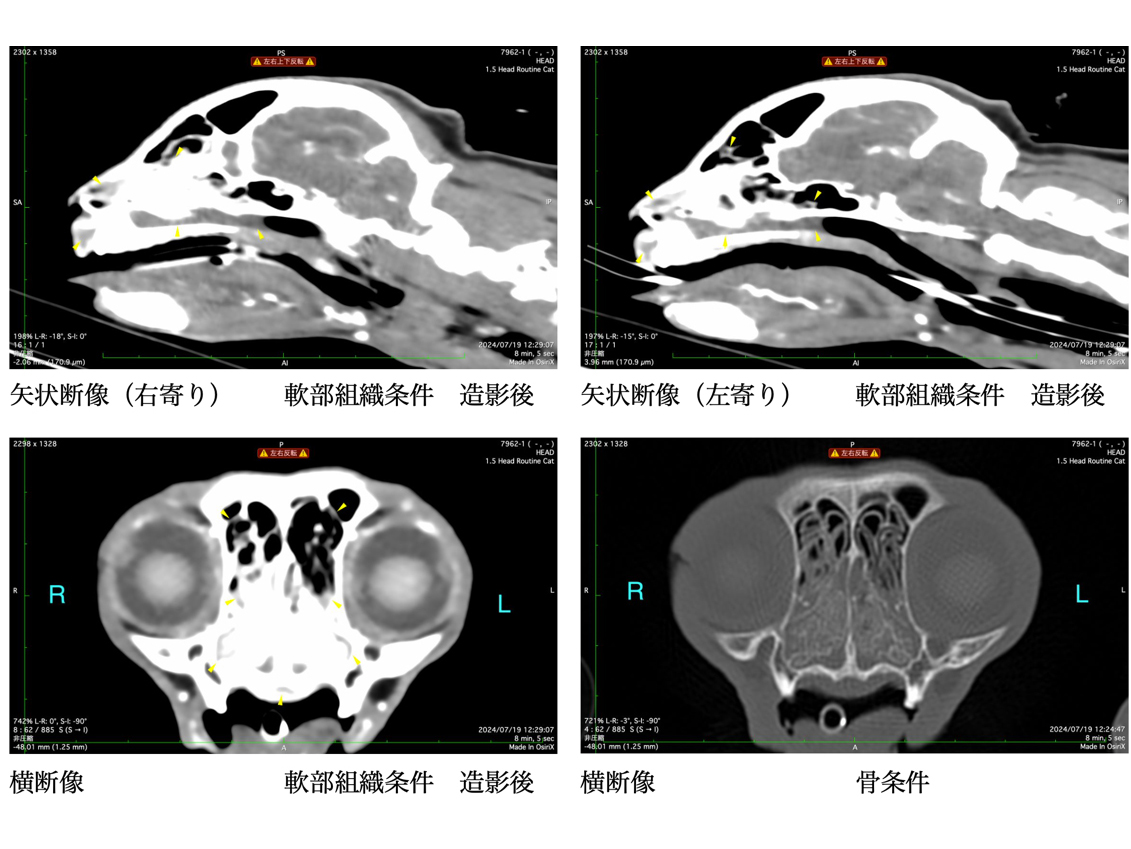

数日前に散歩後より急性の鼻炎症状および鼻出血が認められ、鼻腔内異物の存在を強く疑いました。 精査のためにレントゲン検査およびCT検査を実施し、鼻腔内異物および歯根膿瘍の疑いが示されました。 その後、鼻腔内視鏡を用いて異物の摘出および関連する抜歯を実施しました。

CT検査を実施し腫瘍性疾患を否定